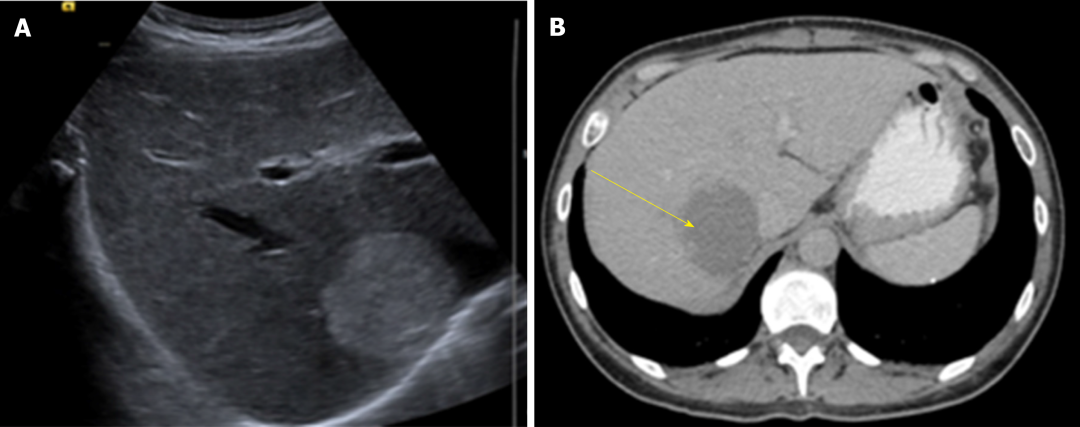

诊断:HH的诊断目前主要依赖于影像学检查,多种检查手段联合应用可提高诊断准确率。常规首选超声检查,再结合CT、MRI以及数字减影血管造影检查等综合判断。

图1 肝脏超声(A)和腹部CT(B)